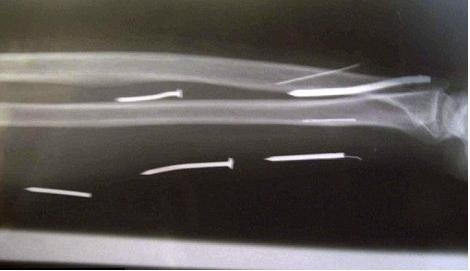

Η 49χρονη Λ.Τ. Αριγιαουάθι επέστρεψε στην πατρίδα της, τη Σρι Λάνκα, και κατήγγειλε τα όσα έζησε στις αρμόδιες Αρχές. Μάλιστα, στο νοσοκομείο όπου νοσηλεύεται, διαπιστώθηκε πως είχε 24 καρφιά στο κορμί της! Τα περισσότερα καρφιά εντοπίστηκαν στα χέρια και τα πόδια της γυναίκας.